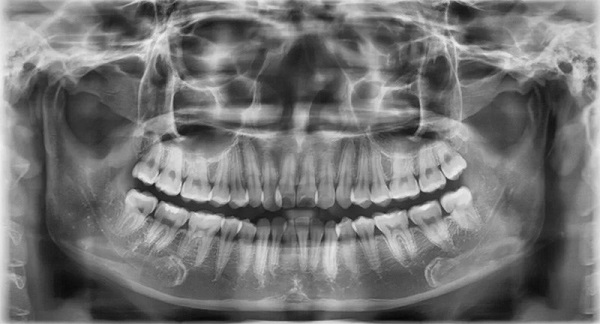

Chụp X quang toàn cảnh răng (chụp Panorama răng)

Đây là phương pháp chụp X quang được sử dụng để kiểm tra toàn bộ khoang miệng. Bằng cách sử dụng kỹ thuật chụp cắt lớp vi tính, nha sĩ có thể thấy rõ răng và mô xương. Trong quá trình chụp, bệnh nhân sẽ được bảo vệ bằng áo chì và cố định trên máy để thu được hình ảnh sắc nét của răng và xương hàm dưới.

Hình ảnh Panorama răng là một công nghệ chụp X quang cho thấy rõ về xương hàm trên và dưới, các thành phần lân cận như khớp thái dương hàm, xoang mũi. Kỹ thuật này cũng cho phép bác sĩ nhìn thấy toàn bộ hai cung răng trên một phim giúp chẩn đoán nhiều loại bệnh lý răng miệng như răng mọc lệch, răng mọc ngầm, u nang, áp xe và tổn thương xương hàm.

Ưu điểm của kỹ thuật Panorama răng là thời gian chụp nhanh, hình ảnh chất lượng cao, an toàn và phù hợp với mọi đối tượng, bao gồm cả trẻ em – nhóm khách hàng khó chụp X quang bằng các phương pháp truyền thống. Tuy nhiên, điểm trừ của phương pháp này là không phát hiện được những vấn đề như lỗ sâu răng, gãy xương, nhiễm trùng,…